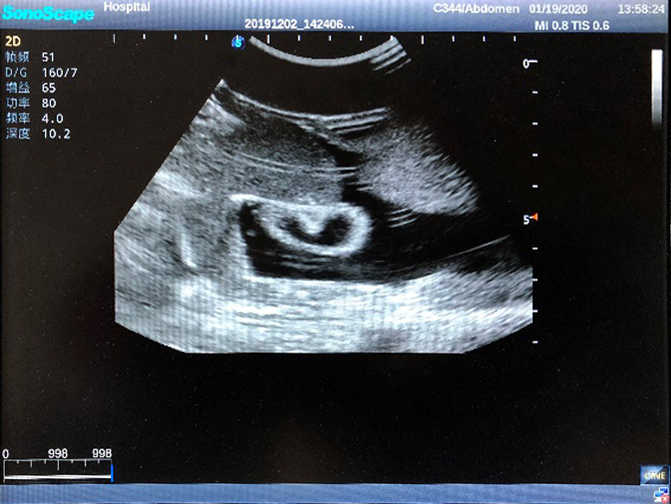

1)  Ideal for trainings like ultrasound-guided abdominocentesis with visible ascites flowing out, ultrasound-guided femoral artery & venous puncture

2)  High quality ultrasound image with clear structures like gallbladder, liver, intestines, arteries and veins etc.

5)  Normal & pathological ultrasound live and intestine models inside